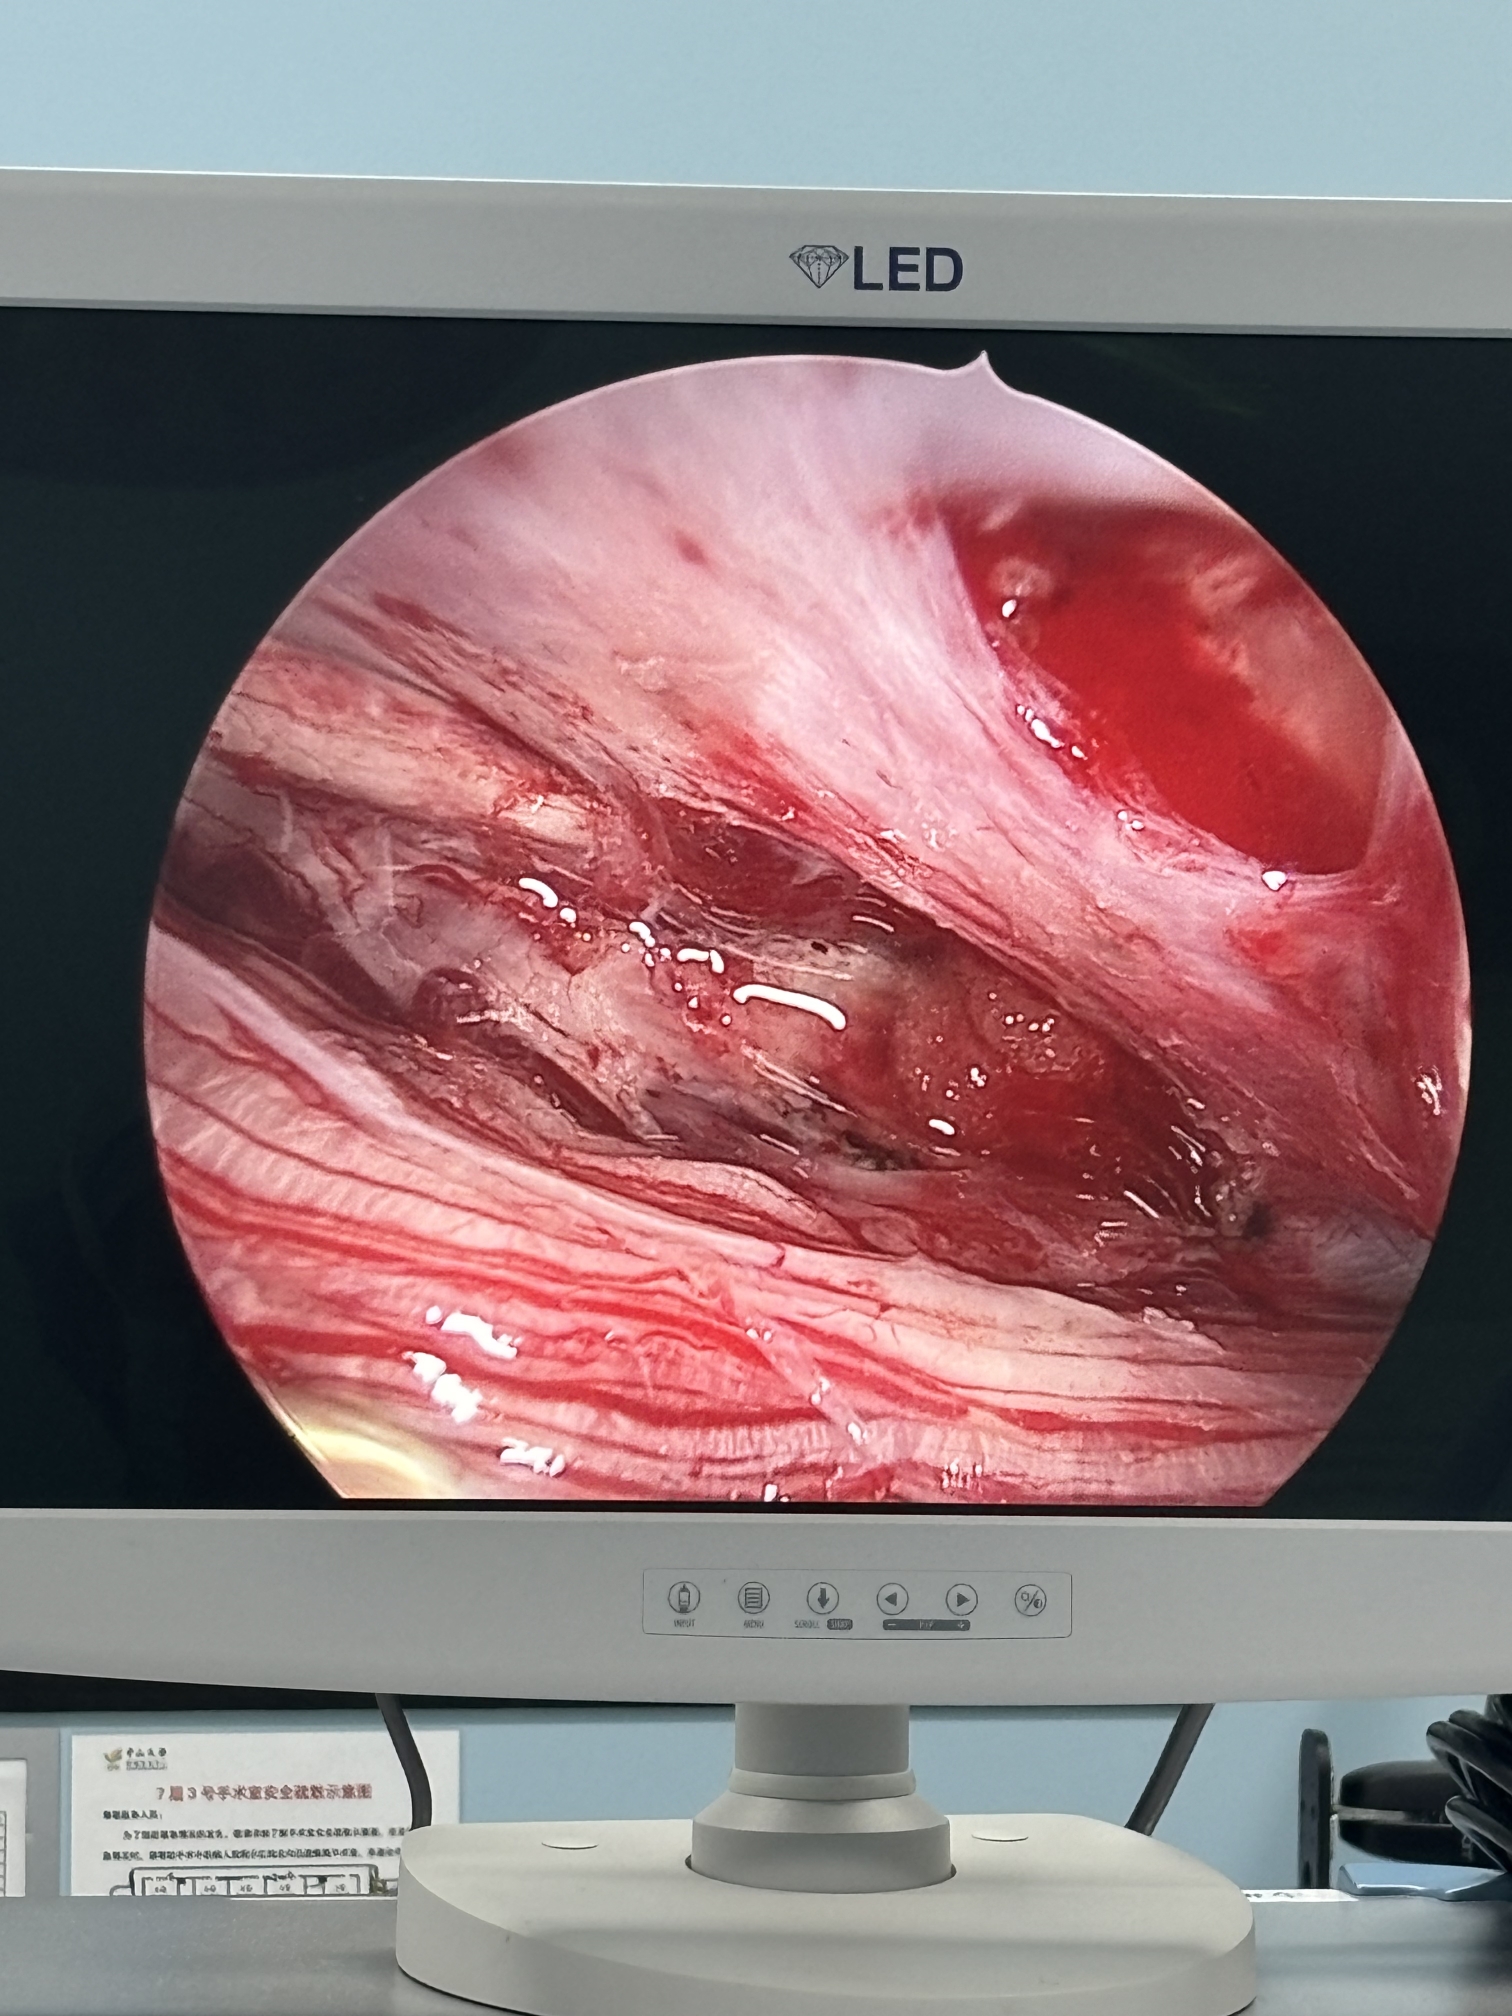

膝关节疼痛,原因是椎管内肿瘤,哑铃型生长,全切肿瘤,保留神经,疼痛症状消失…